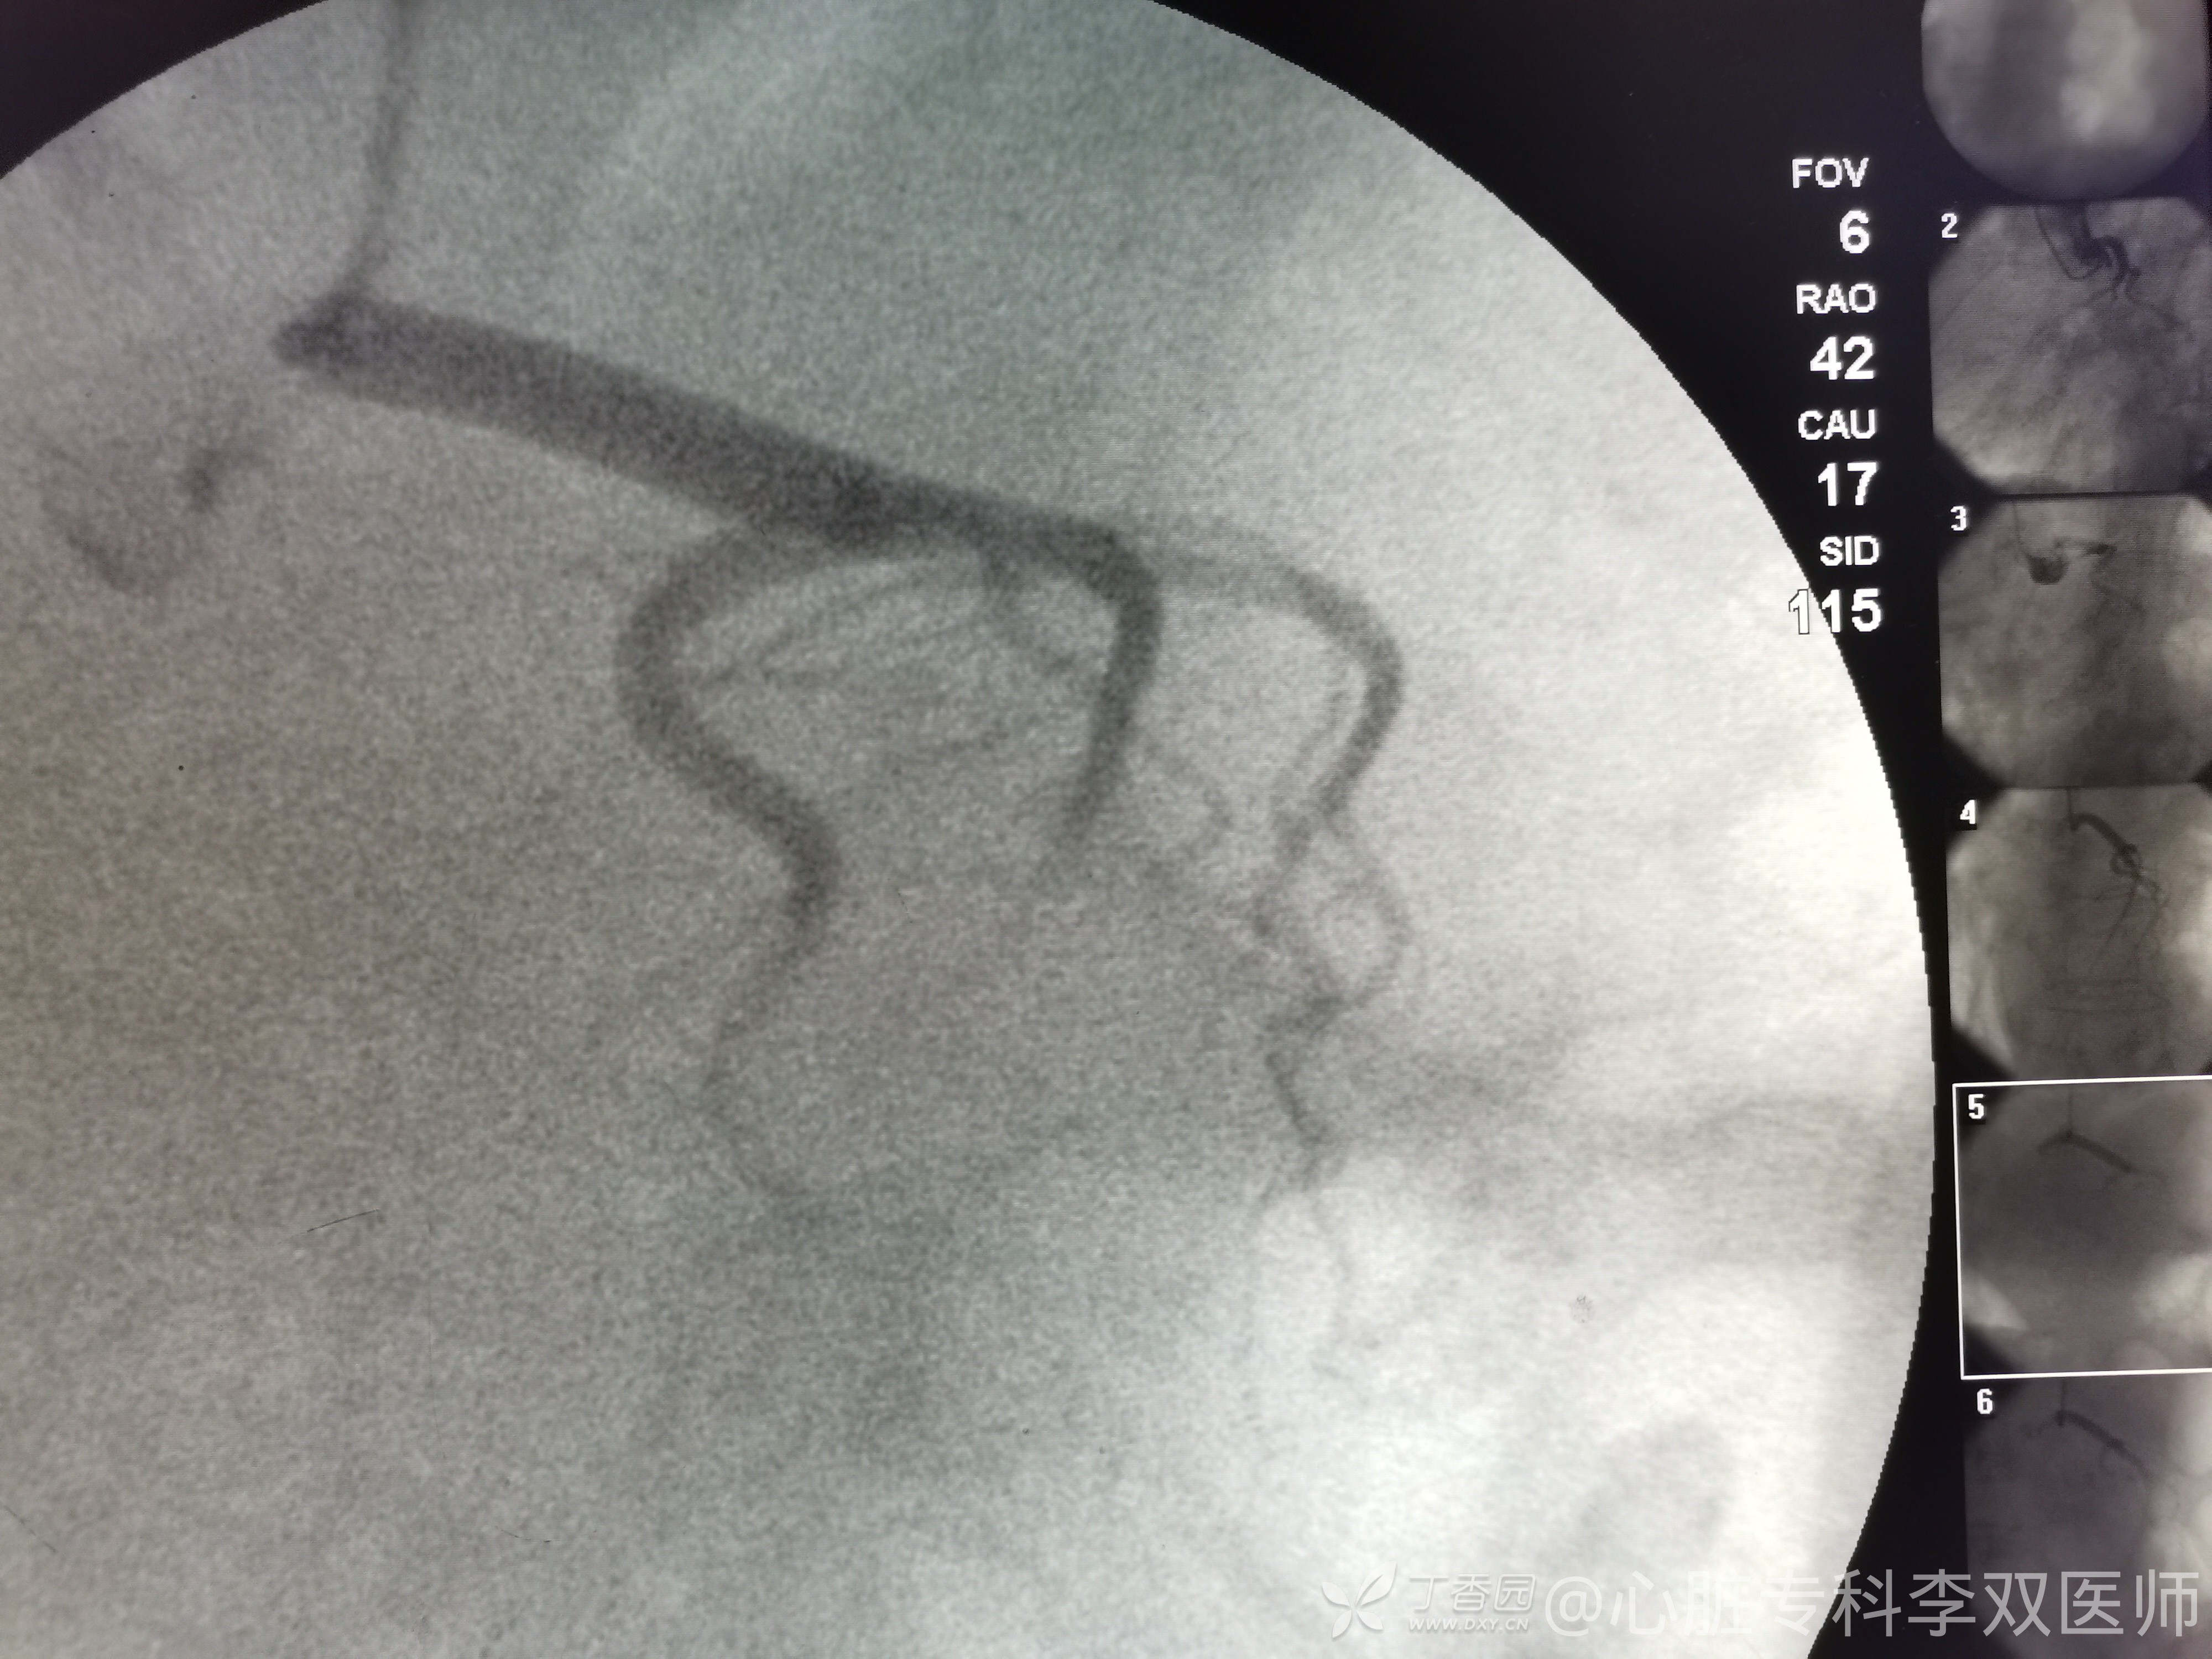

病例右位心的冠脉造影:蛮有意思的!

心血管内科医师 · 发布于 2021-07-13 · 来自 Android · IP 上海上海